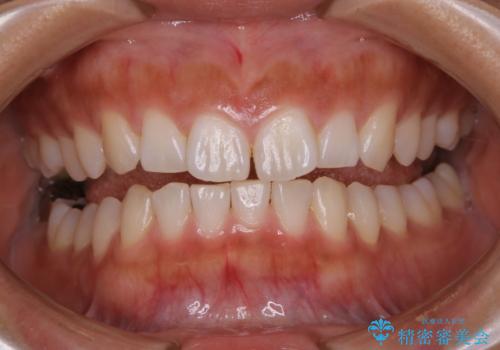

この患者様は、歯科矯正に1、2年かかり矯正中はホワイトニングをすることが出来ないため、歯を白くしてから矯正治療にすすみたいとのことでオフィスホワイトニングを行いました。1回の施術で2.3トーン白くなり、とても白くなりました。ホワイトニングは何度も重ねて白くしていくのですが、1度で満足のいく色見になったため一旦様子を見ることにしました。

1ヶ月後来院して頂きチェックしたところ、やはり後戻りがあったため、再度オフィスホワイトニングを行うことになりました。

1回のオフィスホワイトニングですとこのくらいの後戻りがあるため、ホワイトニングを考えている方は是非参考にしてください。